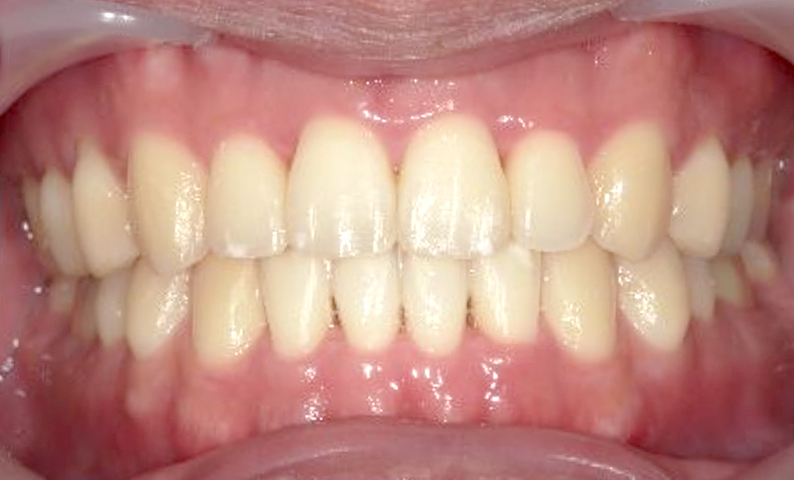

| 治療前 | 治療後 |

|---|---|

|